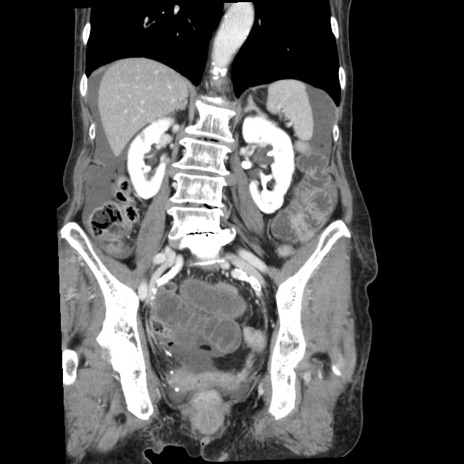

症例1(冠状断像)

【症例】80歳代女性

【主訴】腹痛

【現病歴】8時間前から腹痛あり来院。

【既往歴】糖尿病、脂質異常症、子宮体癌にて子宮全摘術

【身体所見】意識清明・会話良好だが腹痛で苦悶様、全腹部にわたって反跳痛と圧痛あり

【データ】WBC 13600、CRP 0.14、LDH 224、CK 90